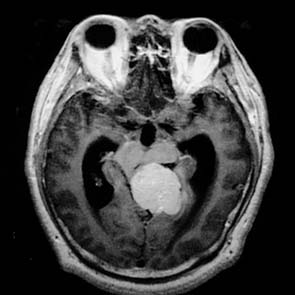

依靠傳統的頭顱平片、腦血管造影和腦室造影診斷多發腦膜瘤是比較困難的。當今,套用CT和MRI便可比較容易地確診顱內多發腦膜瘤(圖1)。

CT或MRI檢查,CT平掃可以很容易地發現那些體積較大,發生於大腦凸面、矢狀竇旁、腦室內及後顱窩的腦膜瘤,但發生於顱底的、體積較小的腫瘤不易發現,因此強化CT掃描是有必要的,尤其是患者的臨床症狀比較複雜臨床與影像學不一致的情況下。多發腦膜瘤在CT或MRI的表現與單發腦膜瘤的特徵相同。CT可以清楚地發現腦膜瘤的鈣化,尤其在混合型或纖維型腦膜瘤較多見。CT還可顯示腫瘤的囊變及其四周腦水腫這種情況常常發生在富於血管的腦膜瘤。

在MRI的T1像上,差不多30%的腦膜瘤為低信號60%為等信號。T2像上腦膜瘤的信號不一致,約50%為等信號,40%表現為高信號。注射對比劑對提高圖像的分辨能力是很有幫助。